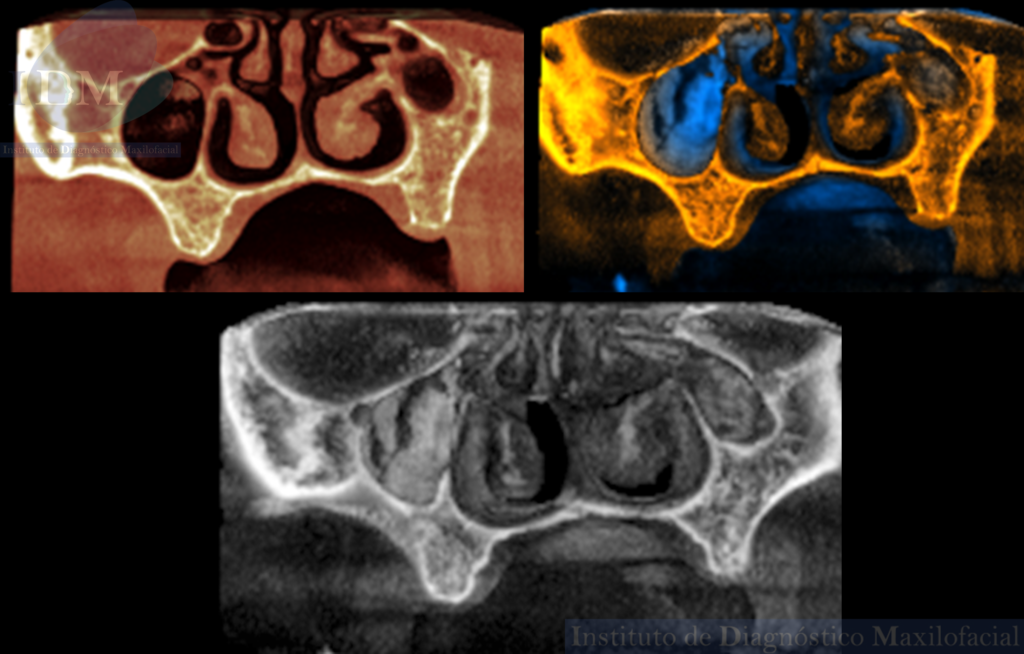

A la evaluación de la tomografía computarizada de haz cónico de campo mediano se observa la disminución de la longitud cefalo caudal y antero posterior del seno maxilar del lado izquierdo en comparación a su contralateral (visto en los cortes coronales y axiales respectivamente).

Asimismo, se observa el engrosamiento de la mucosa antral a predominio de la pared posterior que a su vez presenta una imagen hiperdensa de forma irregular compatible con probable Antrolito. Finalmente, en zonas edéntulas de premolares y molares del segundo cuadrante se observa el trabeculado óseo característico del maxilar superior que debería estar ocupado por el seno maxilar.

RECONSTRUCCIÓN 3D